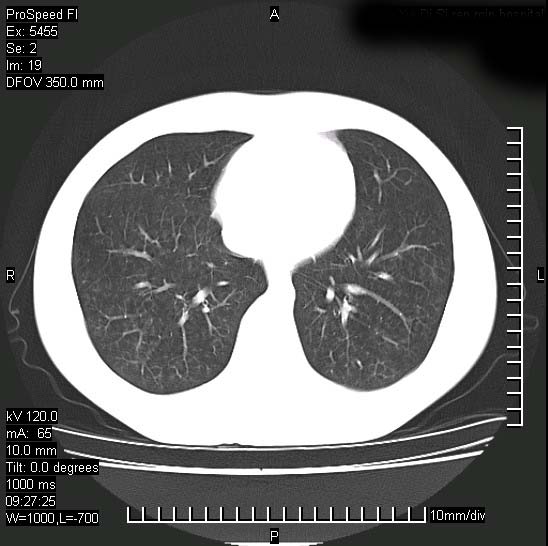

以下是引用zjzjr在2008-12-3 20:50:00的发言:[br]考虑泛细支气管肺炎,建议进一步检查除外肺出血性疾病如含铁血黄素沉着症、肺肾综合征等。

以下是引用zjzjr在2008-12-3 20:50:00的发言:[br]考虑泛细支气管肺炎,建议进一步检查除外肺出血性疾病如含铁血黄素沉着症、肺肾综合征等。

以下是引用光线在2008-12-3 20:19:00的发言:[br]双肺间质性改变。